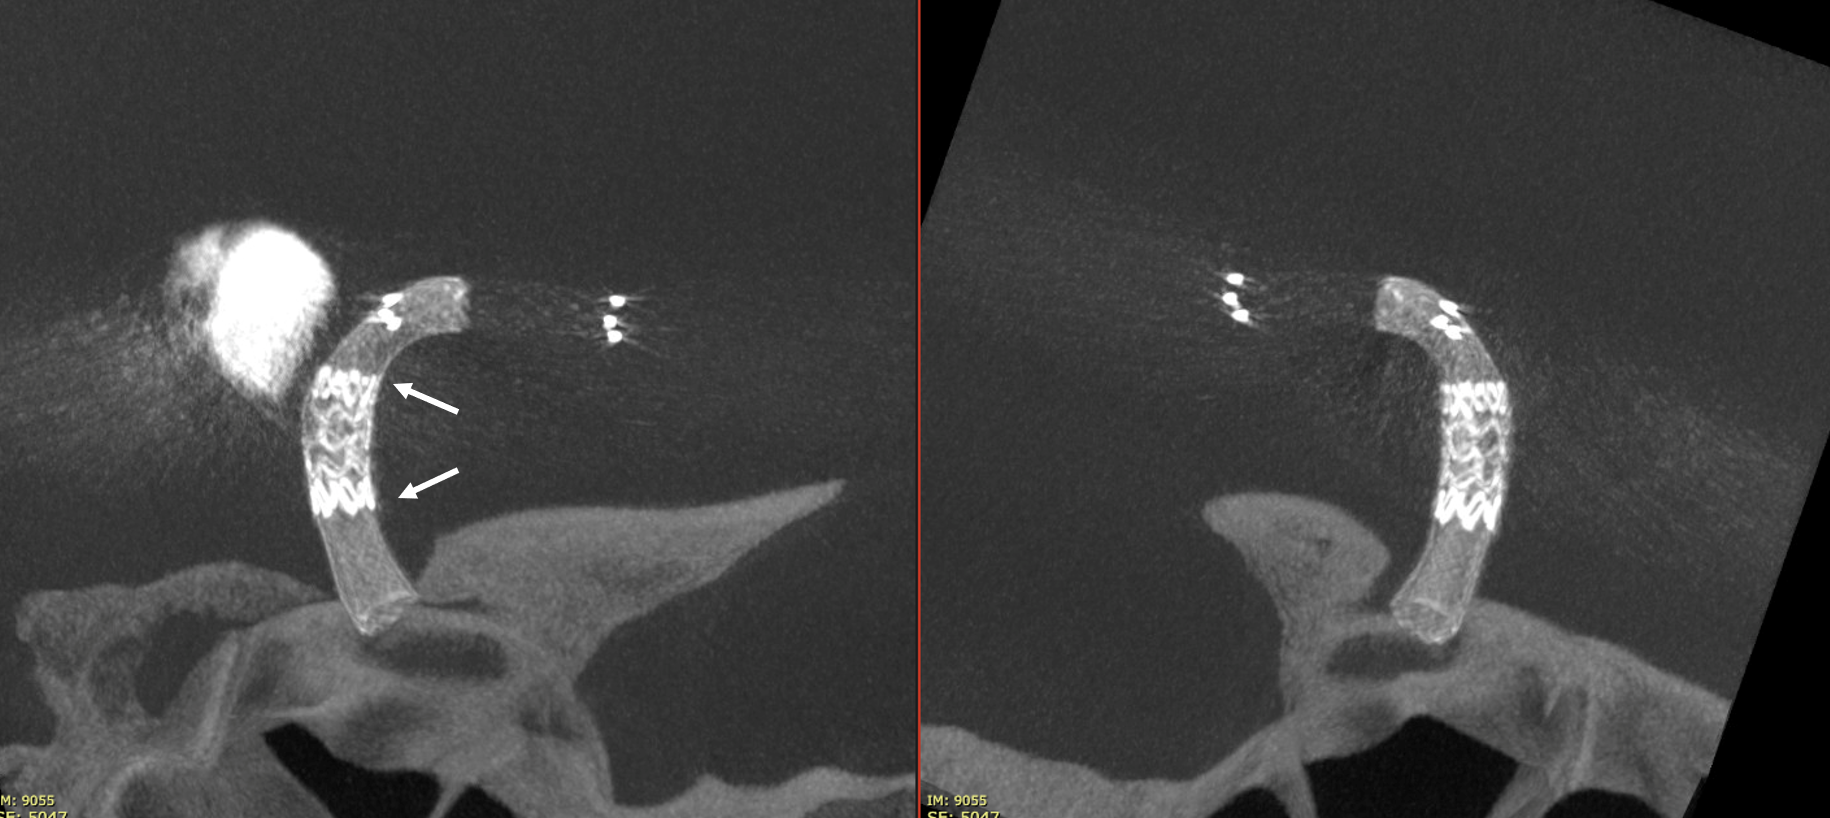

Not injected Vaso-CT, 22 cm FOV 20 seconds acquisition, followed by a secondary reconstruction with 50% FOV and 5123 resolution; Thick MIP. In this case, a Pcom aneurysm, a Derivo 2Heal was used. After the stent release, a minimum distal fish mouthing was seen, so we decided to immediately add a Pegasus stent.

We can see the struts of the Pegasus irregularly open in the carotid bifurcation. We can even recognize the typical distal end of the Derivo with the folded wires.

Noncontrast Vaso-CT, 22 cm FOV 20 seconds acquisition, followed by a secondary reconstruction with 50% FOV and 5123 resolution; Thick MIP.

Wide neck MCA trifurcation aneurysm.

Y stenting with Atlas and Lvis Evo, in emergency. The Atlas diameter was too large because of the temporary limited availability in our centre; we can clearly see the struts of the Atlas too open at the level of the aneurysm neck (arrow). Even the microcatheter for coiling is fully visible jailed by the Lvis Evo in M1

The injection of contrast medium (250 mg/ml, 50% dilution, manual injection, same reconstruction protocol as previous images) reduces the visibility of the struts — an important point to consider. Not everything is always the same contrast dilution, same injection rate, etc. etc. — you need to know how to vary every parameter to achieve desired results.